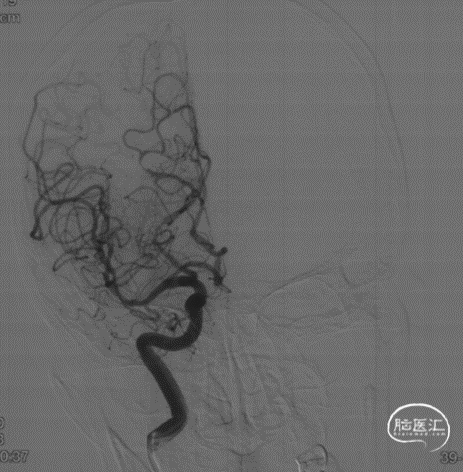

脑血管造影:右侧大脑中动脉中度狭窄。

DSA:远端血管直径2.2mm,近端血管直径2.7mm,狭窄程度约70%,拟行左侧大脑中动脉狭窄支架成型术。

术后正侧位造影显示大脑中动脉血流较术前改善。